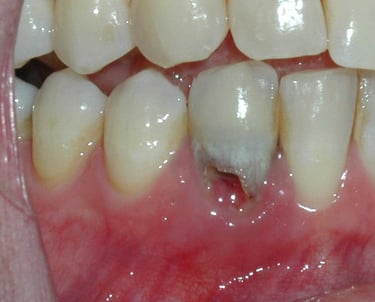

Se revisa si hay fracturas en la parte visible del diente. Las fracturas de la corona pueden ser causadas por trauma o caries extensas y pueden afectar el tratamiento endodóntico.

Evaluación de fracturas de la corona